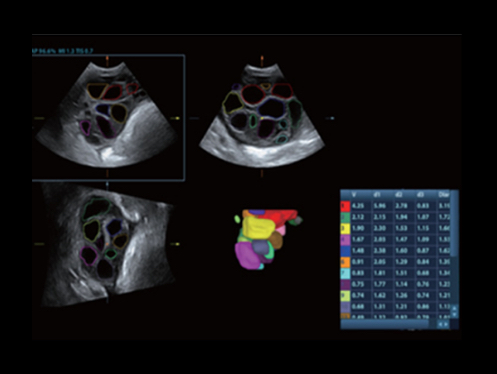

DC-80A con X-Insight mette a disposizione strumenti di una intelligenza eccezionale specifici per la cura della donna, dalla fertilit├Ā allo screening prenatale, e al post partum.

Immagini cliniche